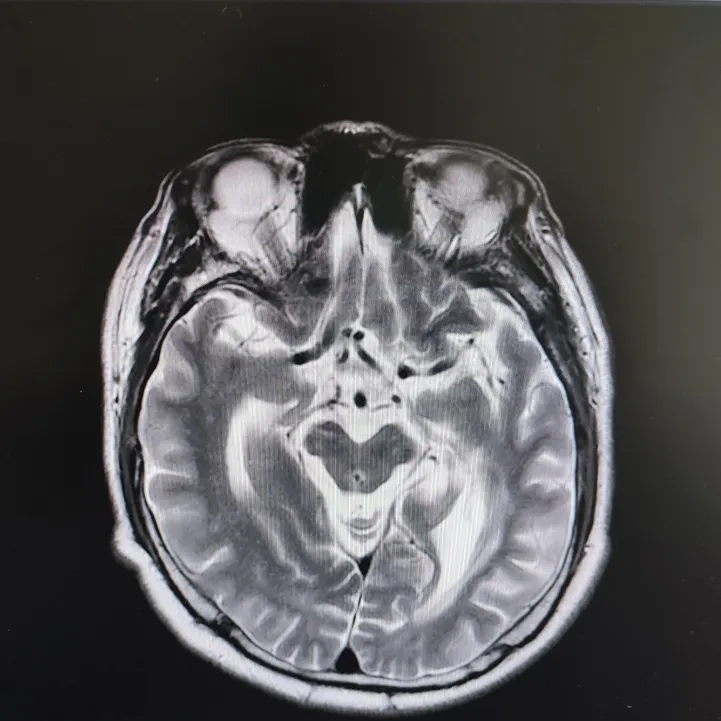

患者头部磁共振影像

就在看似陷入僵局时,关键的血液检查结果出来了——RPR阳性!这个结果像一盏明灯,指明了方向。原来,导致大爷眼病的幕后黑手,竟是由苍白密螺旋体(引起梅毒的病原体)感染引起的神经损害。经过针对性治疗,十几天后,大爷的病情逐渐好转,眼皮能抬起来了,重影消失了,眼球转动也灵活了!